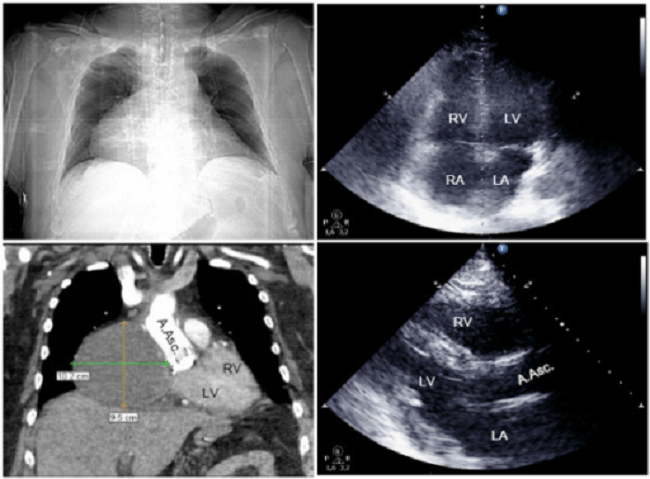

Tamponade jantung adalah gangguan pengisian diastolik jantung akibat sindrom perikardial, dengan karakteristik penurunan curah dan kompresi jantung. Sementara itu, efusi perikardial adalah adanya peningkatan produksi cairan perikardium. Berbeda dengan efusi perikardial, tamponade jantung merupakan sebuah kondisi yang dapat mengancam jiwa yang umumnya disebabkan oleh efusi perikardial dalam jumlah sedang atau besar.[1]

Tamponade jantung terjadi akibat adanya akumulasi cairan pada perikardium, baik serosa, pus, darah, sumbatan, atau gas, yang dapat terjadi akibat inflamasi, trauma, ruptur jantung, atau diseksi aorta.[1,2]